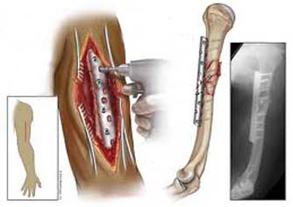

دانش آموخته دانشگاه صنعتی اصفهان برای نخستین بار موفق به طراحی وساخت پلاک استخوانی غیرفلزی و تخریب پذیر جهت استفاده در تثبیت شکستگی استخوان ها در بدن شد.

این طرح که در قالب پایان نامه دکتری خانم انوشه زرگر دانش آموخته دکتری مهندسی مواد دانشگاه صنعتی اصفهان و با راهنمایی دکترمحمد حسین فتحی مديرگروه پژوهشي بيومواد و عضو هیأت علمی دانشکده مهندسی مواد این دانشگاه و دکتر فرود بهمنی عضو هیأت علمی دانشكده پزشكي دانشگاه علوم پزشکی اصفهان ارائه شده است، با استفاده از کامپوزیت پليمر- شیشه زیست فعال، به طراحی وساخت پلاک استخوانی غیرفلزی و تخریب پذیر جهت کاربرد در تثبیت شکستگی استخوان بدن در نواحی تحت بار پرداخته است.

وی با تأکید بر اهمیّت همزمانی بین آهنگ کاهش سفتی و استحکام پلاک با روند التیام استخوان آسیب دیده، به ویژگی های طرح خود اشاره کرد وادامه داد: در این روش پلاک استخوانی غیر فلزی و تخریب پذیر از جنس پلی ال-لاکتیک اسید/شیشه زیست فعال جهت تثبیت شکستگی استخوان های طویل، طراحی، ساخت و مشخصه یابی شده است.

زرگر دستیابی به پلاک تخریب پذیر با خواص مکانیکی مناسب و نرخ تخریب کنترل شده، استحکام، سفتی کششی و خمشی نزدیک به استخوان قشری وکمی بالاتر ازآن در حالت اولیه پلاک (قبل از تخریب)، برخورداری ازقابلیت های تثبیت کنندگی وحمایت از ناحیه شکسته شده و در نتیجه آن جلوگیری از پوکی استخوان و استحکام بیشتر استخوان پس از اتمام فرآیند درمان را از دیگر ویژگی های این طرح بیان کرد.